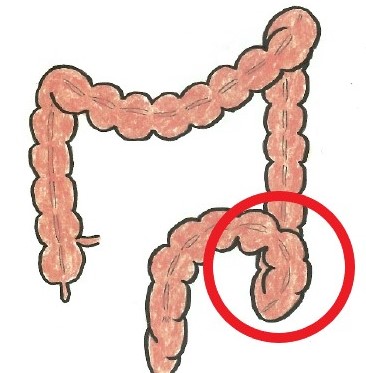

その特定の部分とは

S状結腸という部分です。

名前の通り、S状に曲がりながら上方向に向かうのでどうしても詰まりやすくなります。